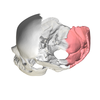

Occipital Bone

know: Foramen Magnum, Occipital Condyles, Superior/ Inferior Nuchal Lines

Cerebellar fossa

Cerebral fossa